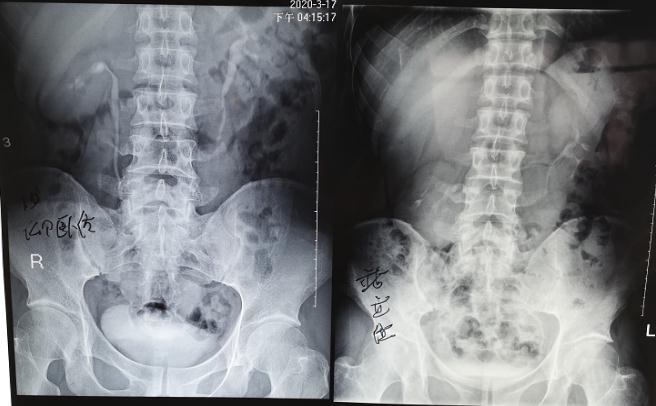

術后靜脈腎盂造影檢查: